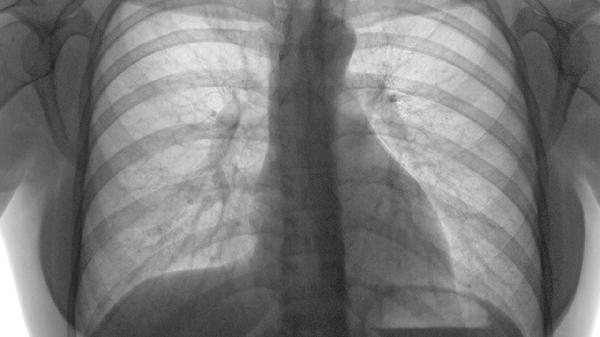

3、X线检查

X线检查主要用于排除肋骨骨折、肺部疾病或胸椎病变等相似症状疾病。典型肋软骨炎在X线下多无异常表现,因为肋软骨在X线下不显影。这项检查对鉴别诊断具有重要意义,可帮助确认肋软骨炎的诊断。